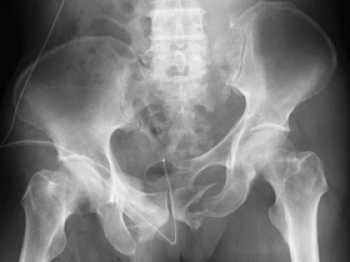

今日、ご紹介するのは、骨盤骨折についてご紹介していきたいと思います。

骨盤は、寛骨(腸骨、坐骨、恥骨)+ 仙骨 + 尾骨 で構成しています。

そして、骨盤は、仙腸関節と恥骨結合部を有した環になっています。

骨盤骨折の分類

骨盤の分類は、大きく2つに別れていて、骨盤の環が保たれているか、離断したものか

①骨盤骨単独骨折

腸骨、坐骨、恥骨に骨折があっても、環の連続性が保たれているもの

②骨盤骨環骨折

前者に比べて骨盤骨が形成する環の連続性が骨折によって離断されたもの

細かくいいますと、剥離骨折(筋腱の牽引によって骨が剥離して起きる骨折)もあります。